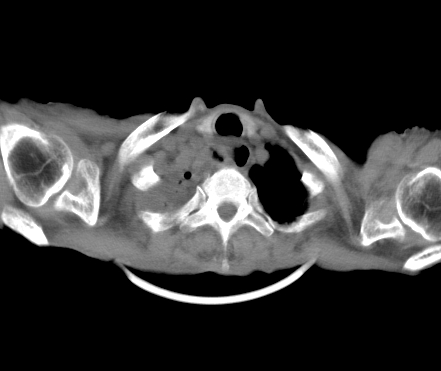

以下是引用gaoshengjiang在2008-5-30 19:53:00的发言:[br]右上叶可见大片实变影,其内可见充气支气管影及囊状影,右上叶尖端支气管走形区可见结节样影,左侧胸腔内可见胸腔胃影。纵隔淋巴结肿大。[br]考虑:1.右上肺阻塞性肺炎伴肺脓肿形成。支持转移所致。[br] 2.左侧胸腔胃。